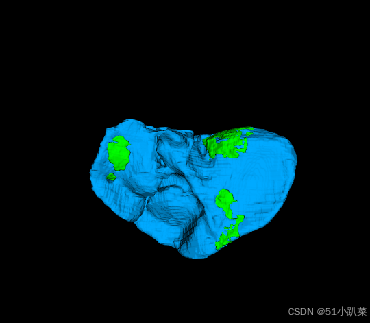

基于Unet分割医学2D3D图像

器官分割和三维重建